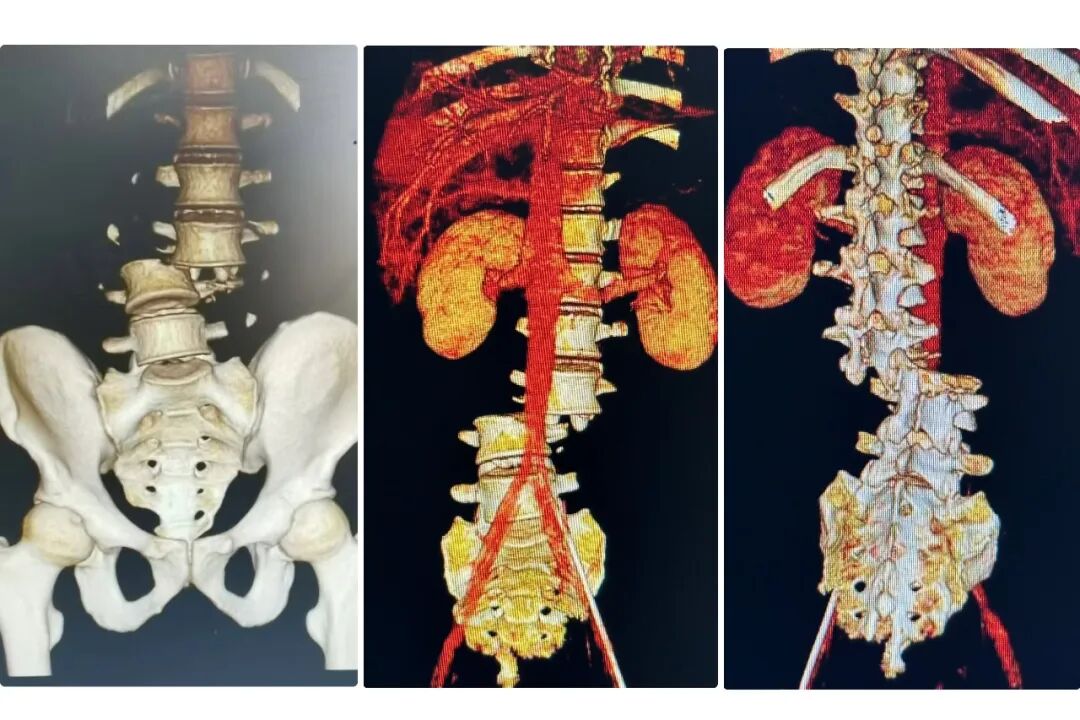

??术前腰椎CT

??通过先进的影像学检查,专家们精确地确定了骨折脱位的部位、程度以及神经受压情况。